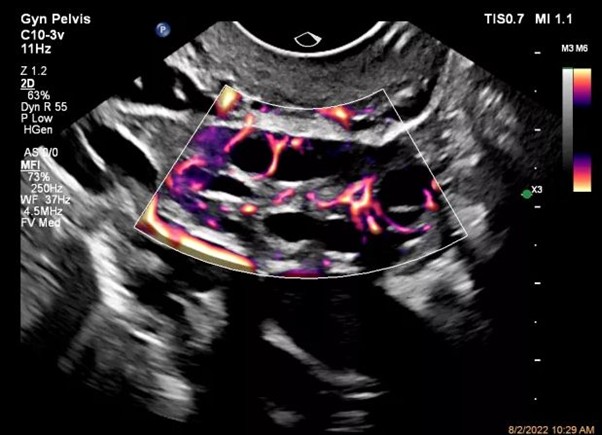

Акустическая безопасность

Ультразвук считается неионизирующим и в целом безопасным методом диагностики, однако врач обязан соблюдать принцип ALARA (As Low As Reasonably Achievable) — минимально необходимой акустической нагрузки на пациента. Это особенно важно при обследовании плода и использовании режимов, генерирующих большое количество энергии, например допплера.

Для контроля акустической нагрузки на экране УЗИ-аппарата постоянно отображаются два параметра:

- Тепловой индекс (TI — Thermal Index)

Показывает потенциальный риск нагрева тканей. Индекс измеряется как отношение акустической мощности, используемой при сканировании, к мощности, необходимой для повышения температуры ткани на один градус Цельсия. Чем ниже TI, тем меньше риск.

- Механический индекс (MI — Mechanical Index)

Показывает потенциальный риск кавитации (образования и коллапса микропузырьков) в тканях, содержащих газ, например в легких или кишечнике. Чем ниже MI, тем ниже риск механического воздействия на ткани.

Для соблюдения ALARA врач должен использовать настолько низкие значения TI и MI, при которых все еще можно получить диагностически значимое изображение. Кроме того, важно сокращать общее время экспозиции, особенно при обследовании плода, а также избегать длительной фокусировки высокой мощности в одной и той же точке.